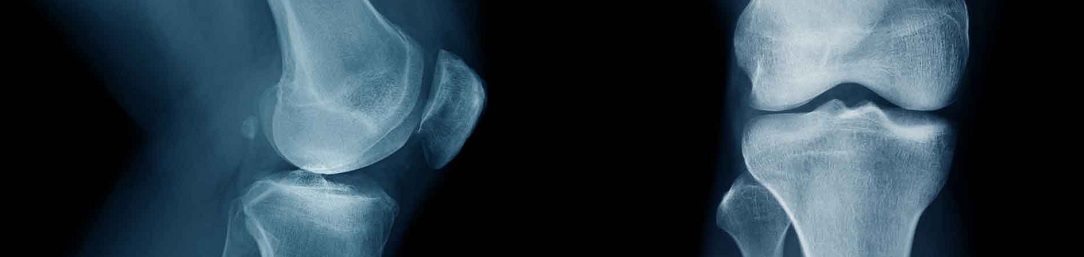

Osgood-Schlatterova choroba

CO JE OSGOOD SCHLATTEROVA CHOROBA (OSD)

Řadí se mezi skupinu úponových bolestí, tzv. entezopatií kolene (spolu s běžeckým či skokanským kolenem či iliotibiálním syndromem):

- aseptická nekróza úponu čtyřhlavého svalu stehenního na hrbol kosti holenní v oblasti kolene.

- výskyt zejména u výrazně aktivně sportujících dětí a juniorů při přetížení růstové ploténky svalového úponu (ta je v tomto věku ještě chrupavčitá a není tak pevná jako kost dospělého stejně sportujícího)

- postihuje zejména děti a bývá označována jako růstové bolesti kolene